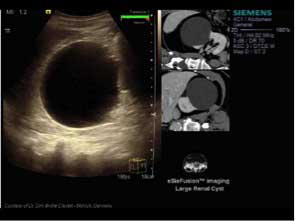

Technology made practical: Advance routine clinical medicine with eSieFusion™ Imaging

Merge CT or MRI 3D data volumes with real-time ultrasound with manual, point, and automated alignment tools.